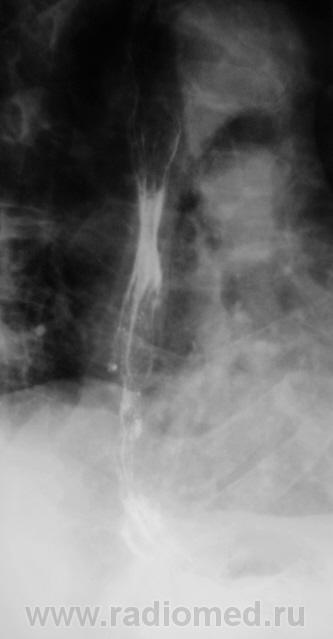

Пациент направлен на рентгенологическое исследование пищевода после ФГДС с диагнозом - "Пищевод Барретта".

Пациент первично был направлен в онкологический диспансер (областной). От туда он был направлен по месту жительства для производства ФГДС, которая и была проведена, был выставлен выше указанный диагноз.

После ФГДС, врач эндоскопист рекомендовал провести рентгеновское исследование пищевода.

1. Пищеводно-желудочный переход отсутствует - это одно из подтверждений пищевода Баррета.

2. Наблюдаемое сужение может быть следствием эзофагеального стеноза в зоне трансформации эпителия - это тоже подтверждение пищевода Баретта, но как без биопсии дифференцировать с инфильтративной формой рака....

3. Нишеподобное выпячивание по левой стенке может быть пептической язвой - это тоже характерно для пищевода Баретта....

4. Изменения в кардиальном отделе желудка по медиальной стенке - интересное и непонятное явление...думаю без биопсии тут никто не разберется, это и отек слизистой, это и рост в просвет...

Вывод, столь серьезная заявка, как пищевод Баретта, тем более с учетом возможности развития на этом фоне опухолевого поражения, требует ОБЯЗАТЕЛЬНОГО гистологического подтверждения....без биопсии НИКУДА....увы...

Циркулярное сужение в н/3 + отсутствие складок на уровне поражения + формирующееся престенотическое расширение = рак н/3 пищевода. Ну, а Барреты? А Барреты потом...